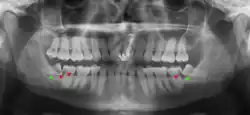

Las muelas del juicio retenidas se clasifican por la dirección de impactación, su profundidad en comparación con la superficie de mordida de los dientes adyacentes y la parte de la corona del diente que atraviesa el tejido gingival o el hueso. Las muelas del juicio impactadas también pueden clasificarse por la presencia o ausencia de síntomas y enfermedad. La detección de la presencia de muelas del juicio suele comenzar al final de la adolescencia, cuando una muela parcialmente desarrollada puede quedar retenida. La exploración suele incluir un examen clínico y radiografías panorámicas.

El diagnóstico de impactación se puede hacer clínicamente si es visible una parte suficiente de la muela del juicio para determinar su angulación y profundidad, y si el paciente es lo suficientemente mayor como para que sea improbable una erupción o enderezamiento posterior. Las muelas del juicio continúan moviéndose hasta la edad de 25 años debido a la erupción, y luego continúan algún movimiento posterior debido a la enfermedad periodontal.[18]

Si el diente no se puede evaluar únicamente con el examen clínico, el diagnóstico se realiza mediante una radiografía panorámica o una tomografía computarizada de haz cónico. Cuando las muelas del juicio no erupcionadas todavía tienen potencial de erupción, se utilizan varios factores predictivos para determinar la probabilidad de que los dientes se impacten. La relación de espacio entre la longitud de la corona del diente y la cantidad de espacio disponible, el ángulo de los dientes en comparación con los otros dientes son los dos predictores más utilizados, siendo la relación de espacio la más precisa. A pesar de la capacidad de movimiento en la edad adulta temprana, la probabilidad de que el diente se impacte puede predecirse cuando la relación entre el espacio disponible y la longitud de la corona del diente es inferior a 1.:[5] 141

No existe una norma para detectar las muelas del juicio. Se ha sugerido, a falta de pruebas que apoyen la retención o extracción rutinaria de las muelas del juicio, que la evaluación con radiografía panorámica, comenzando entre los 16 y los 25 años de edad, se realice cada 3 años. Una vez que exista la posibilidad de que los dientes desarrollen una enfermedad, se recomienda una discusión sobre los riesgos operativos frente al riesgo a largo plazo de la retención con un cirujano oral y maxilofacial u otro clínico capacitado para evaluar las muelas del juicio. Estas recomendaciones se basan en pruebas de nivel de opinión de expertos.[19] Puede ser necesaria la exploración a una edad más temprana si los segundos molares (los "molares de los 12 años") no erupcionan, ya que la posición ectópica de las muelas del juicio puede impedir su erupción. Las radiografías pueden evitarse si la mayor parte del diente es visible en la boca.